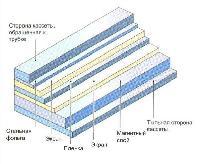

Мобильный рентгенаппарат + оцифровщик. Получение рентгеновского изображения на экране ноутбука. Вариант за 1,4 миллиона рублей под ключ.

Мобильный рентгенаппарат с печатью рентгенограмм на рентгеновской пленке. Цена 700000 рублей.